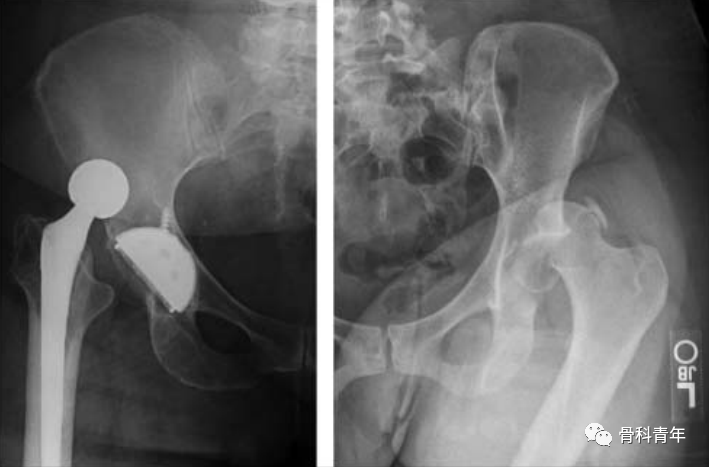

髋关节后脱位影像图。左图示全髋置换术后髋关节脱位,右图示创伤性髋关节后脱位,伴有髋臼后壁骨折